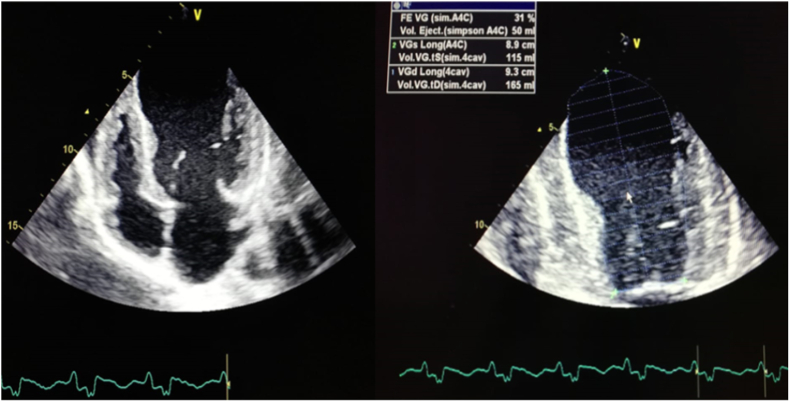

Trans Thoracic Echocardiogram (TTE) showed an aspect of dilated cardiomyopathy (DCM), with a systolic dysfunction (EF at 31%) and a global hyperkinesia (Fig. 2).